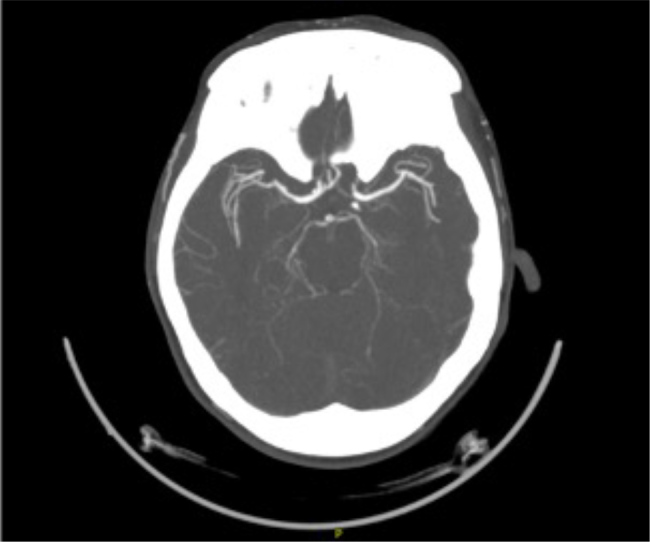

Case description: A 45-year-old female with diabetes, hypertension and multiple ischaemic strokes presented with altered consciousness due to hypoglycaemia. Initial workup at a different hospital suggested cerebral vasculitis based on the findings of cerebral angiography. She had negative systemic vasculitis markers and was treated with corticosteroids and rituximab and discharged. On admission to our facility, an MRI of the brain revealed multiple infarcts of varying ages, and a CTA showed arterial beading, suggestive of primary CNS vasculitis. CSF analysis demonstrated elevated protein and IgG without pleocytosis. Despite high-dose corticosteroids and rituximab, she developed progressive neurological deterioration with new infarcts in the vertebrobasilar territory, leading to brainstem dysfunction and brain death.

Learning points: Physicians should be alert in diagnosing primary CNS vasculitis in a young patient with recurrent strokes affecting multiple vascular territories, particularly when systemic vasculitis markers are negative.Imaging studies, such as MRI and computed tomography angiography (CTA), play an essential role in diagnosing primary CNS vasculitis, with findings such as arterial beading and a multi-infarct pattern helping differentiate it from atherosclerotic diseases.Early recognition and aggressive high-dose corticosteroid and immunosuppressive (rituximab) therapy are essential in primary CNS vasculitis, as delayed treatment can result in rapid neurological deterioration, as seen in this case.